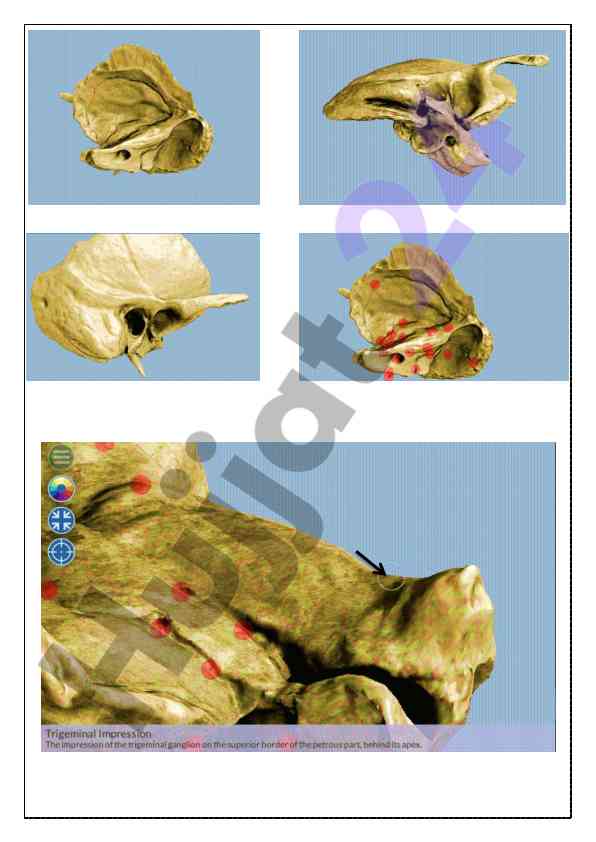

Kalla skeleti va chakka suyagi haqida umumiy ma'lumotlar taqdim etilgan o‘quv qo‘llanma. Anatomiyaga oid asosiy tushunchalar va strukturalar izohlangan.